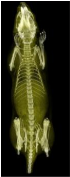

Super Nova系统扫描小鼠骨骼三维图像

Super Nova系统CT扫描实验鼠三维图像